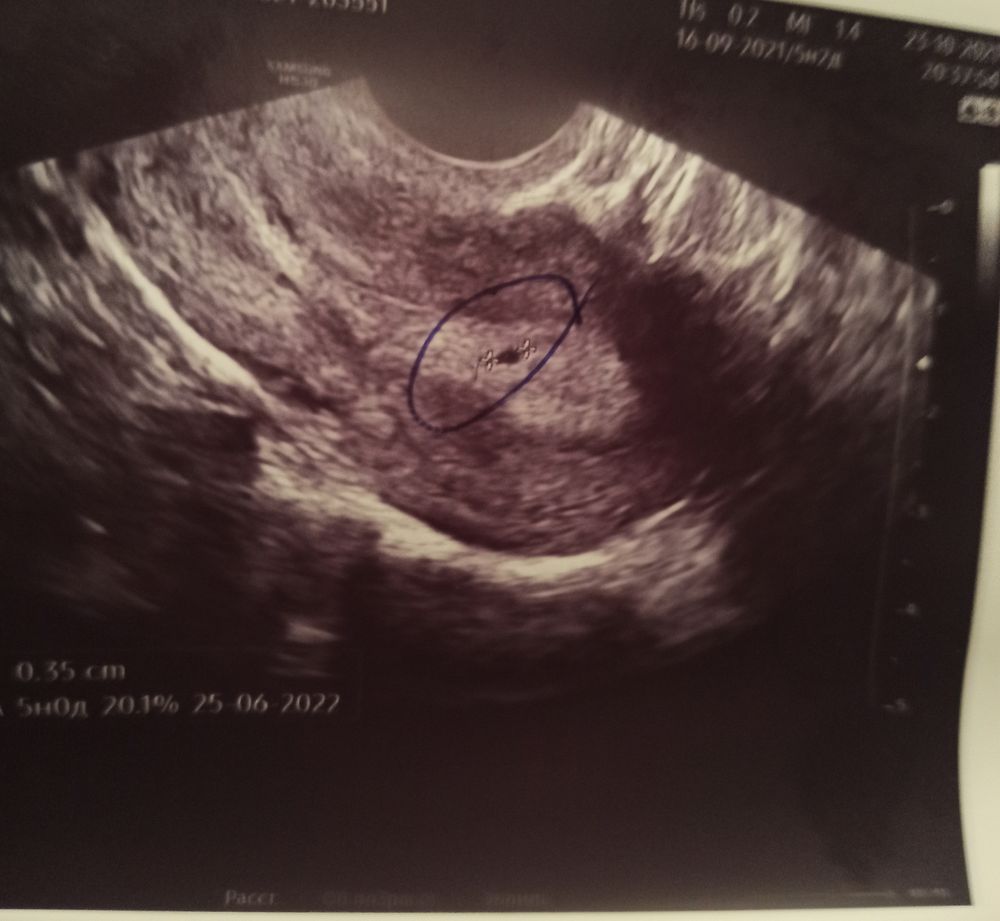

На УЗИ плодное яйцо в матке. ХГЧ отрицательный.

Девочки, может ли быть это киста или беременность? Я вообще не знаю что думать. УЗИ показывает одно, а тесты и ХГЧ отрицает. В платной клинике делала УЗИ, беременность поставили под вопросом. Сегодня пойду в гинекологию на полноценный осмотр. Очень волнуюсь.